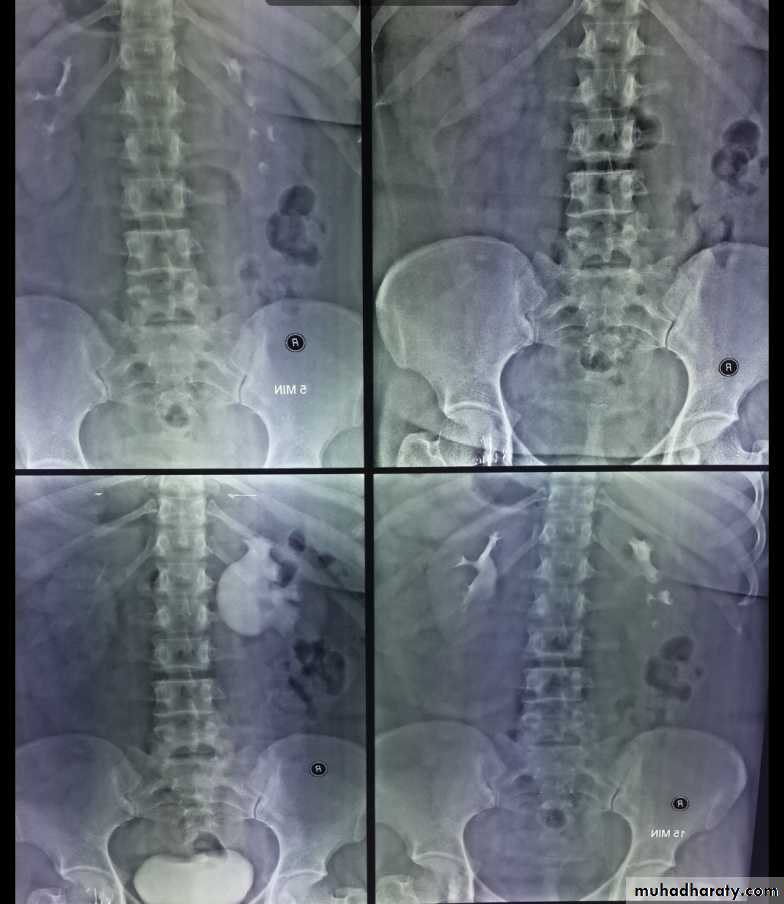

• Films timing:

• 1.Plain film (KUB): to identify calcifications in the urinary tract region

• 2.immediate film: taken immediately after contrast injection& it is aimed to show the nephrogram (contrast in renal parenchyma), may be omitted to decrease radiation dose

• 3.five min. film: to determine if excretion is symmetrical(calices appear at the same time on both sides). After this film, compression band applied around the patient

• 4.15 min. film: to show the PCS adequately

• distended with opaque urine. After this film,

• compression band is released

• 5.post compression film: to show the whole

• urinary tract.

• 6.post voiding film: to assess residual urine,

• & to confirm ureterovesical junction stone